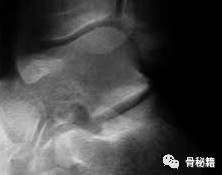

1. 侧位像。在侧位片上有 2 个非常重要的影像学标记

Böhler’s 角:评价跟骨高度和关节压缩情况;

Gissane’s 角:评价跟骨前、中和后关节面的相对位置改变。